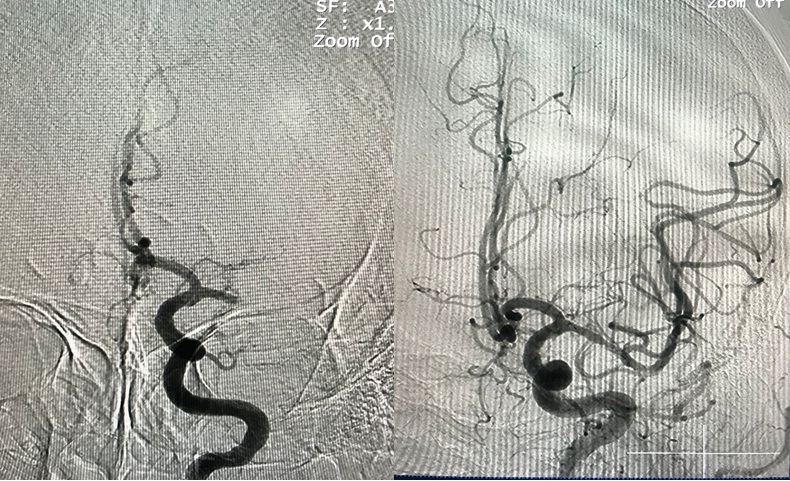

Hình: ĐM não giữa trái trước và sau lấy huyết khối

- Sau can thiệp B/N liệt cải thiện (cơ lực tay chân 3/5)

Hình: ĐM cảnh trong trái trước và sau lấy huyết khối (còn tắc M1 trái)

Hình: Sau lấy huyết khối hoàn toàn Cảnh trong và M1 trái và các cục huyết khối được lấy ra.